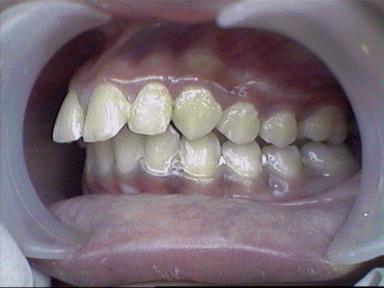

Malocclusion [Div.II]

After Treatment Intra Oral